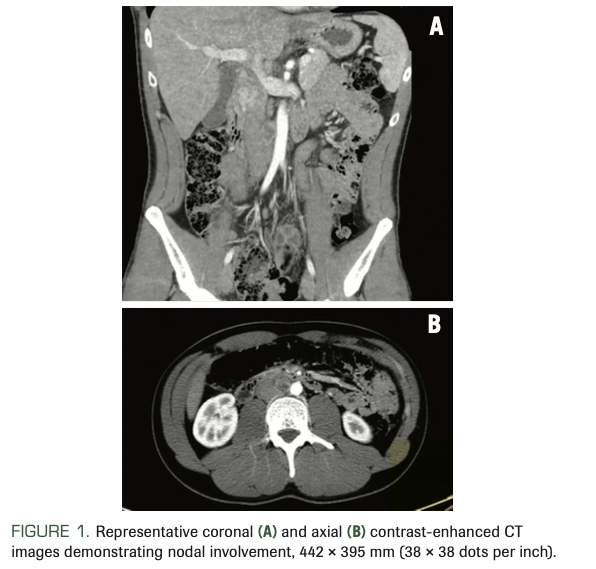

A man, aged 21 years, presented with a 4-month history of progressive swelling of the right testicle. Ultrasound revealed a heterogenous solid mass in the right testicle suspicious for malignancy. Further work-up included CT scans, which identified a 2-cm retroperitoneal lymph node; there was no evidence of thoracic metastases (Figure 1). Serum tumor markers revealed a mildly elevated α-fetoprotein (AFP) and normal lactate dehydrogenase (LDH) and human chorionic gonadotropin (hCG).

FIGURE 1. Representative coronal (A) and axial (B) contrast-enhanced CT images demonstrating nodal involvement, 442 × 395 mm (38 × 38 dots per inch).